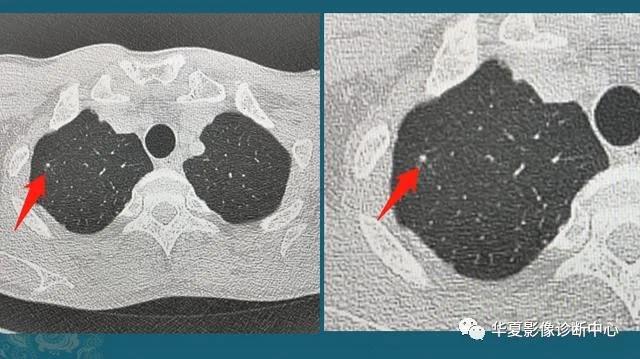

下图是两位女士,左图是当年在萤石矿上打工,当时条件简陋防护不到位,长期吸入粉尘,在肺里形成很多小结节:

右图是一位采棉女工,长期吸入植物性粉尘,在肺里形成很多微结节和索条状影。

类似的尘肺病包括13种,包括矽肺、煤工尘肺、焊工尘肺等。既往尘肺分为致纤维性尘肺(危害大)和非致纤维性尘肺,矽肺、石棉肺、滑石尘肺为致纤维性尘肺;而吸入某些金属粉尘(如铁、钼),在肺组织内呈现一般的异物反应,脱离粉尘后可以逐渐减弱,对人体危害较小。